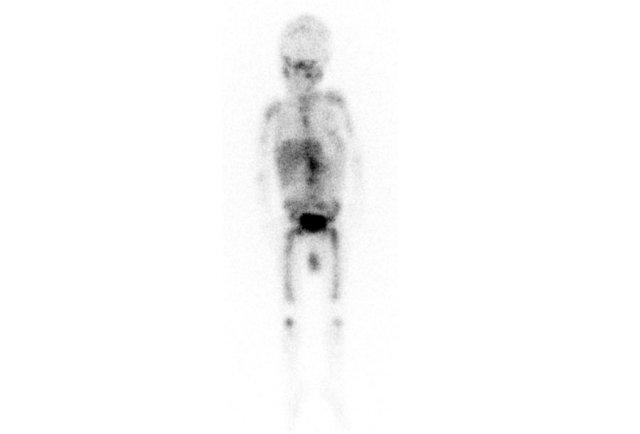

MIBG

All the activity indicates bone metastases.

Trong theo dõi hình ảnh học của u nguyên bào thần kinh đã di căn, kết quả có thể khá khó diễn giải, vì các di căn xương có thể trở nên rõ ràng hơn khi chúng được điều trị thành công.